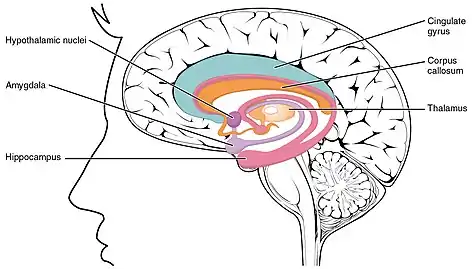

The limbic system, also known as the paleomammalian cortex, is a set of brain structures located on both sides of the thalamus, immediately beneath the medial temporal lobe of the cerebrum primarily in the forebrain.[1]

The limbic system is involved in lower order emotional processing of input from sensory systems and consists of the amygdala, mammillary bodies, stria medullaris, central gray and dorsal and ventral nuclei of Gudden.[3] This processed information is often relayed to a collection of structures from the telencephalon, diencephalon, and mesencephalon, including the prefrontal cortex, cingulate gyrus, limbic thalamus, hippocampus including the parahippocampal gyrus and subiculum, nucleus accumbens (limbic striatum), anterior hypothalamus, ventral tegmental area, midbrain raphe nuclei, habenular commissure, entorhinal cortex, and olfactory bulbs.[3][4][5]

Currently, it is not considered an isolated entity responsible for the neurological regulation of emotion, but rather one of the many parts of the brain that regulate visceral autonomic processes.[9] Therefore, the set of anatomical structures considered part of the limbic system is controversial. The following structures are, or have been considered, part of the limbic system:[10][11]

- Cortical areas:

- Limbic lobe

- Orbitofrontal cortex: a region in the frontal lobe involved in the process of decision-making

- Piriform cortex: part of the olfactory system

- Entorhinal cortex: related to memory and associative components

- Fornix: a white matter structure connecting the hippocampus with other brain structures, particularly the mammillary bodies and septal nuclei

- Subcortical areas:

- Septal nuclei: a set of structures that lie in front of the lamina terminalis, considered a pleasure zone

- Hippocampus and associated structures: play a central role in the consolidation of new memories

- Amygdala: located deep within the temporal lobes and related with a number of emotional processes

- Nucleus accumbens: involved in reward, pleasure, and addiction

- Diencephalic structures:

- Hypothalamus: a center for the limbic system, connected with the frontal lobes, septal nuclei, and the brain stem reticular formation via the medial forebrain bundle, with the hippocampus via the fornix, and with the thalamus via the mammillothalamic fasciculus; regulates many autonomic processes

- Mammillary bodies: part of the hypothalamus that receives signals from the hippocampus via the fornix and projects them to the thalamus

- Anterior nuclei of thalamus: receive input from the mammillary bodies and involved in memory processing